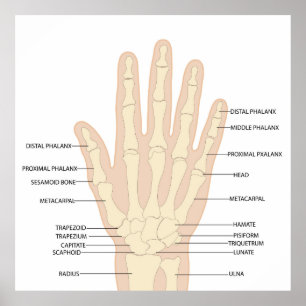

Anatomie der menschlichen Hand Poster

PreisCHF 102.00